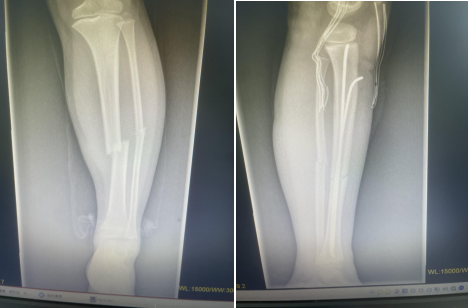

因此,该技术是一种微创、安全、有效、并发症少的内固定方法,适用于儿童长骨干横形、斜形及短螺旋形骨折,对肱骨和股骨近、远端干骺端骨折及桡骨颈骨折如应用得当也可获得满意的治疗效果。目前,弹性髓内钉技术在国内外已成为儿童四肢长骨干闭合性骨折治疗的首选方法。

术后应使用石膏或支具固定 6~8,尤其是不稳定性骨折。石膏或支具固定有助于缓解疼痛和减少膝关节周围软组织激惹。当X线片上有连续骨痂出现,可开始部分负重行走。弹性钉取出时间可根据骨折愈合时间及功能恢复情况而定,学龄期儿童寒暑假期间取出内固定为宜。弹性钉留置时间过长,可能会增加取出的难度。股骨干骨折4~5个月可获得坚强愈合;肱骨和胫骨通常需要 3~4 个月;尺桡骨双骨折约 6 个月可获得坚强愈合。而干骺端骨折通常 6~8 周愈合,术后 3 个月即可取出内固定。(骨二科)